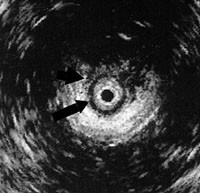

Undersøkelser gjort før og etter operasjonen fremgår av tabell 1. Behandlingsresultatet ble vurdert median 8 måneder (2 – 43 måneder) etter operasjonen. Subjektive plager ble vurdert ut fra kontinens for fast avføring, løs avføring og for luft. Perineums høyde og eventuelle arrforandringer ble vurdert ved inspeksjon. Ved palpasjon ble tykkelsen av og eventuelle defekter i sfinkter vurdert. Sfinktertonus i hvile og under knip ble registrert både ved digital eksplorasjon og ved analmanometri. Transanal ultralydundersøkelse (fig 1) ble utført for å få et visuelt inntrykk av sfinkterskadens lokalisasjon og utbredning.

Pasienter med inkontinens bør forsøke bekkenbunnstrening hos fysioterapeut, eventuelt også biofeedbacktrening (24). Dersom betydelige inkontinensproblemer vedvarer, bør pasienten henvises til senter med kompetanse og utstyr for utredning. Klinisk undersøkelse er vanligvis tilstrekkelig for å stille diagnosen, men ultralydundersøkelse med analprobe må gjøres for å avklare sfinkterskadens lokalisasjon og omfang (16). Hvis ultralydundersøkelse viser en distinkt, avgrenset defekt i sfinkter, er sfinkterplastikk den aktuelle behandling. Anal manometri bør utføres for å få et objektivt mål på sfinkterfunksjonen, og måling av nerveledningshastighet i pudendalnervene er en nyttig tilleggsundersøkelse for å se om det foreligger en nevrogen skade. Flere studier tyder på at resultatene etter sfinkterplastikk er dårligere dersom det påvises nedsatt ledningshastighet i en eller begge pudendalnerver (9, 11, 25).